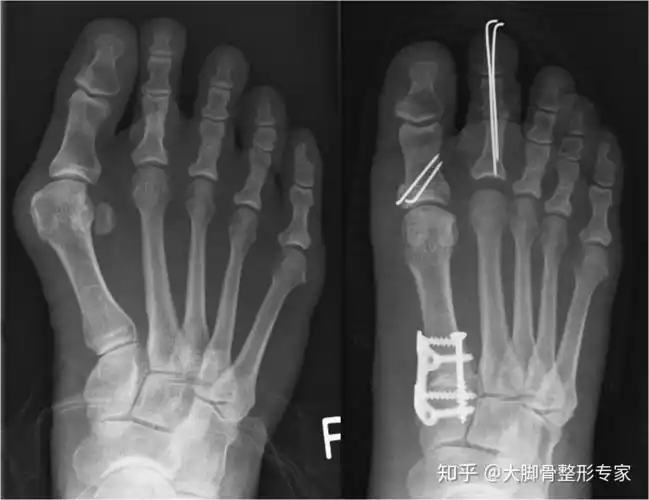

既然是一跖骨偏斜导致了大脚骨,那就需要通过截骨等方式将一跖骨掰直

在临床选择中有很多种方法,根据跖骨截骨部位大致分为远端截骨,中段截